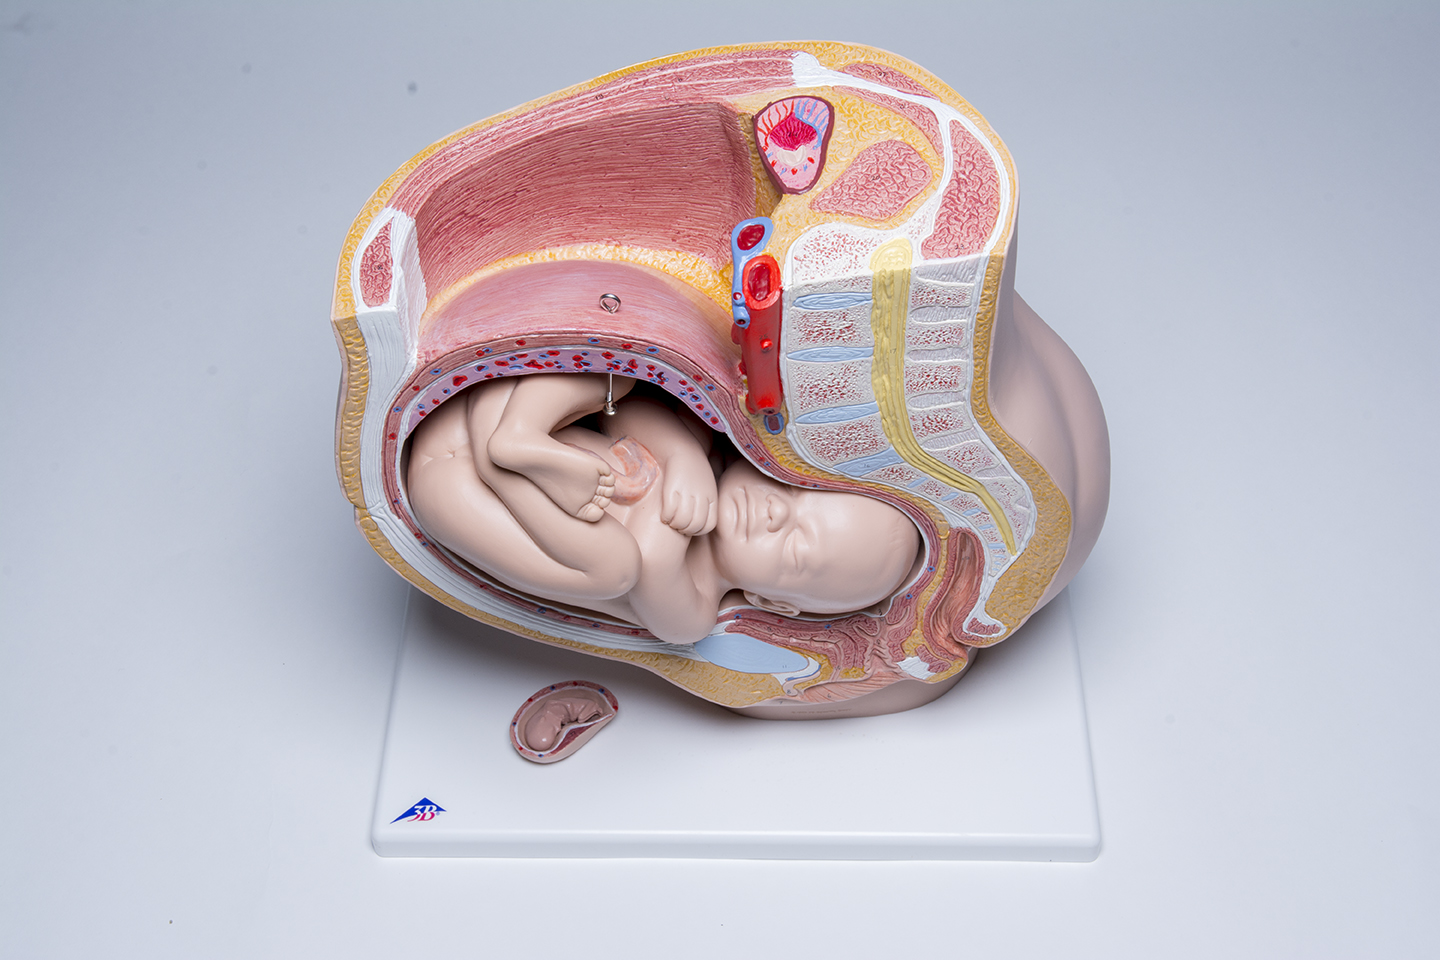

Pelvic Anatomy Pregnancy Model

This anatomy pregnancy model is a representation of a median section through the female pelvis at 40 weeks pregnant with a removable fetus. Study the normal position of child before birth with this model plus the human reproductive and urinary systems. A uterus with embryo in 3rd month of pregnancy is mounted on base for added detail. The realistic and high quality female pelvis includes the female genital organs and other important anatomical details. This pregnancy female pelvis is a great addition to any anatomy classroom or clinician’s office to educate about the effects of pregnancy.

This pelvic anatomy pregnancy model allows the clinician to easily explain what is taking place internally during pregnancy and how it affects surrounding organs, muscle and bone. This will enable to clinician to point out the many issues that can arise from childbirth and what can be done proactively to prevent them.